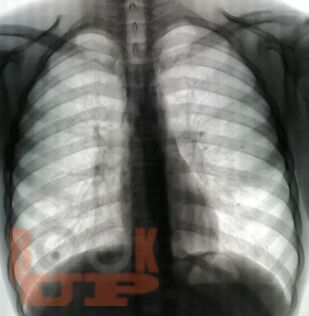

Учебное пособие составлено в соответствии с требованиями ФГОС ВО по специальностям 31.05.01 Лечебное дело и 31.05.02 Педиатрия, рабочей программы дисциплины «Фтизиатрия» (2018). В пособии собраны воедино и обобщены сведения о лучевой диагностике туберкулеза органов дыхания, включена клиническая классификация туберкулеза, иллюстрированная рентгенограммами больных, лечившихся в КГБУЗ «Красноярском краевом противотуберкулезном диспансере №1» с 1980-х г. по настоящее время.